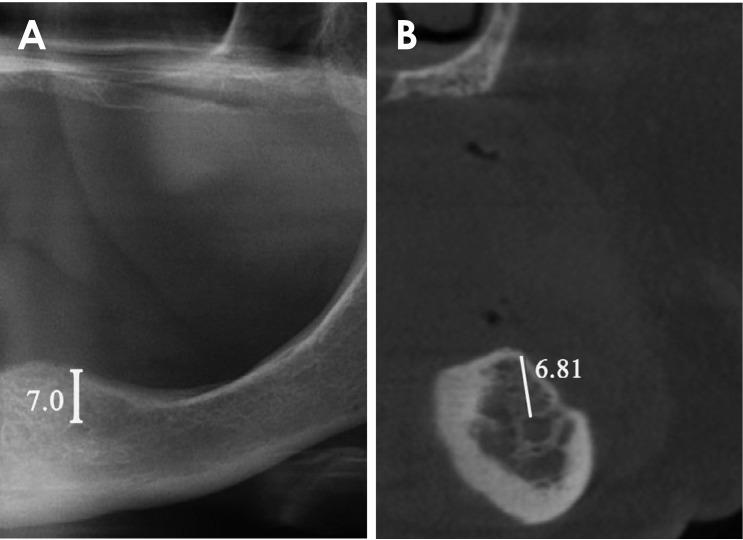

A total of 56 individuals who underwent panoramic radiography and a CBCT evaluation before dental implant surgery were enrolled in the study. Measurements were performed to identify the shortest vertical distance between the alveolar crest and neighboring anatomical structures, including the maxillary sinus, nasal floor, mandibular canal, and foramen mentale. The differences between the measurements on panoramic radiography and CBCT images were statistically analyzed.

Statistically significant differences were observed between the measurements on panoramic radiography and CBCT for all anatomical structures (<.05). The correlation coefficients () between the paired samples obtained from panoramic radiography and CBCT were closely correlated (<.05), with values varying from 0.921 and 0.979 for different anatomical regions.